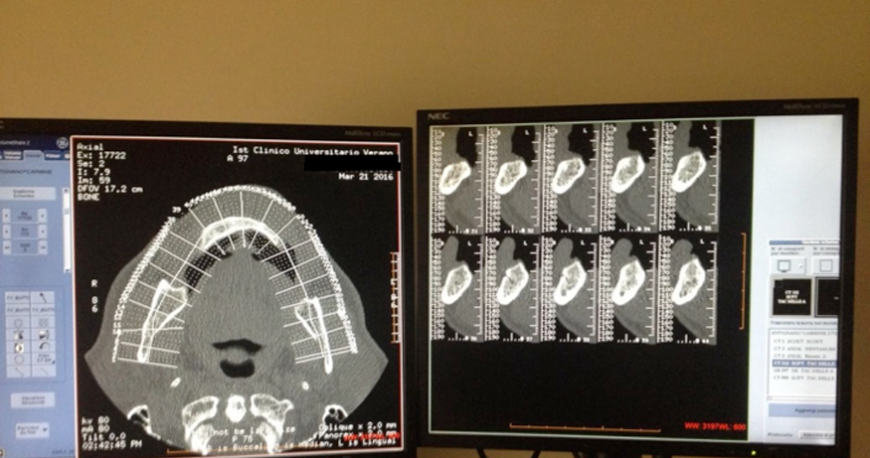

- La Tomografia Computerizzata (TC)